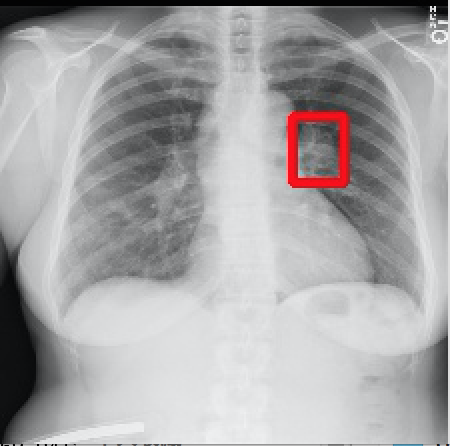

2017年CVPR的一篇“ChestX-ray8”论文[1]首次对医院留存的胸部CT数据库进行人工处理,并通过医学专家分别对8种疾病作标记,形成该领域首个标准的数据库,为胸部医疗的计算机辅助诊断打开了大门,也为后续的研究提供铺垫。CT数据库整理的效果如下图所示,其中红线框内为人工标注的疾病区域:

Atelectasis Cardiomegaly Effusion Infiltrate

Mass Nodule Pneumonia Pneumothorax

图2.1 胸部数据集示例

目前为止,数据集已经达到了14个疾病的分类结果,每张图的大小为1024×1024,少数图片附有由专家标注的病理区域,数据集共有112120张图片,来源于30805个不同的病人,其中51708张图片被标注有疾病,其余则为无病。可以看出无病的数据较多,对有病的特征学习可能较低,相关的学习加速收敛的方法将在2.4节讲解。